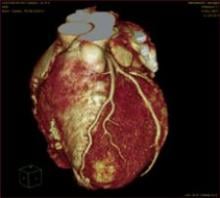

It is based on decades-old tomogram technology; even more surprising is the concept behind it is inspired in part by formulas conceived by a mathematician on a blackboard at the turn of the 20th century.